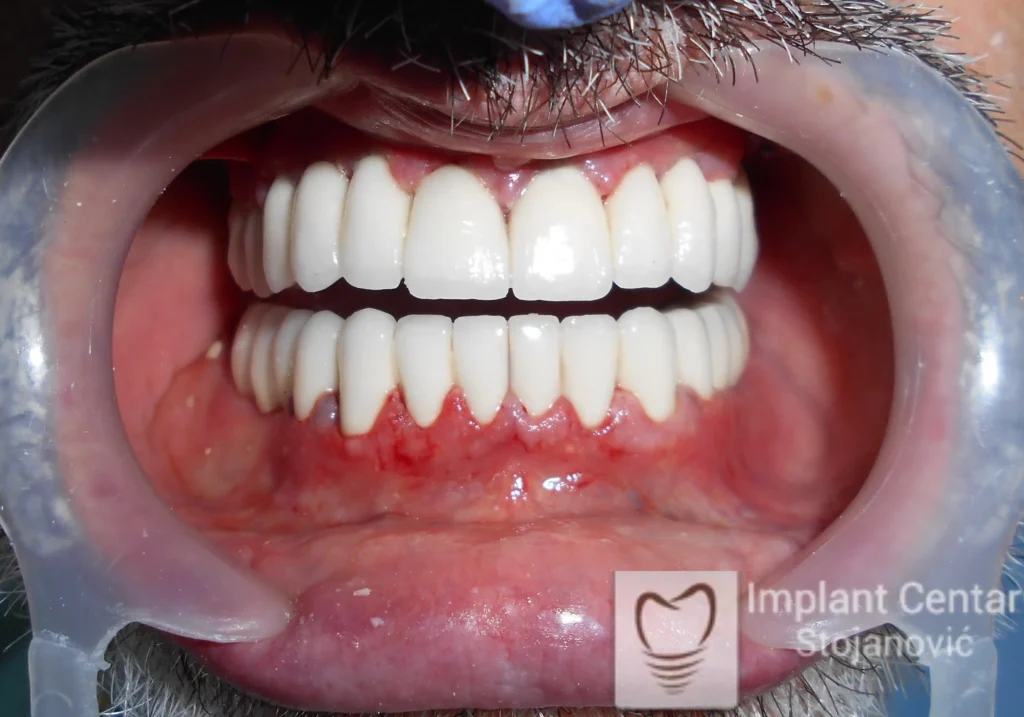

Tokom perioda oseointegracije, pacijent je bio zbrinut fiksnim privremenim krunicama, čime je već pet dana nakon intervencije obezbeđena potpuna funkcionalna i estetska rehabilitacija. Nakon završetka perioda integracije implantata, izrađeni su definitivni cirkonijum-keramički mostovi na implantatima.

Pacijent je izuzetno zadovoljan postignutim rezultatom, navodeći da po prvi put jasno oseća svoje nepce tokom žvakanja, kao i da se smeje sa punim samopouzdanjem.